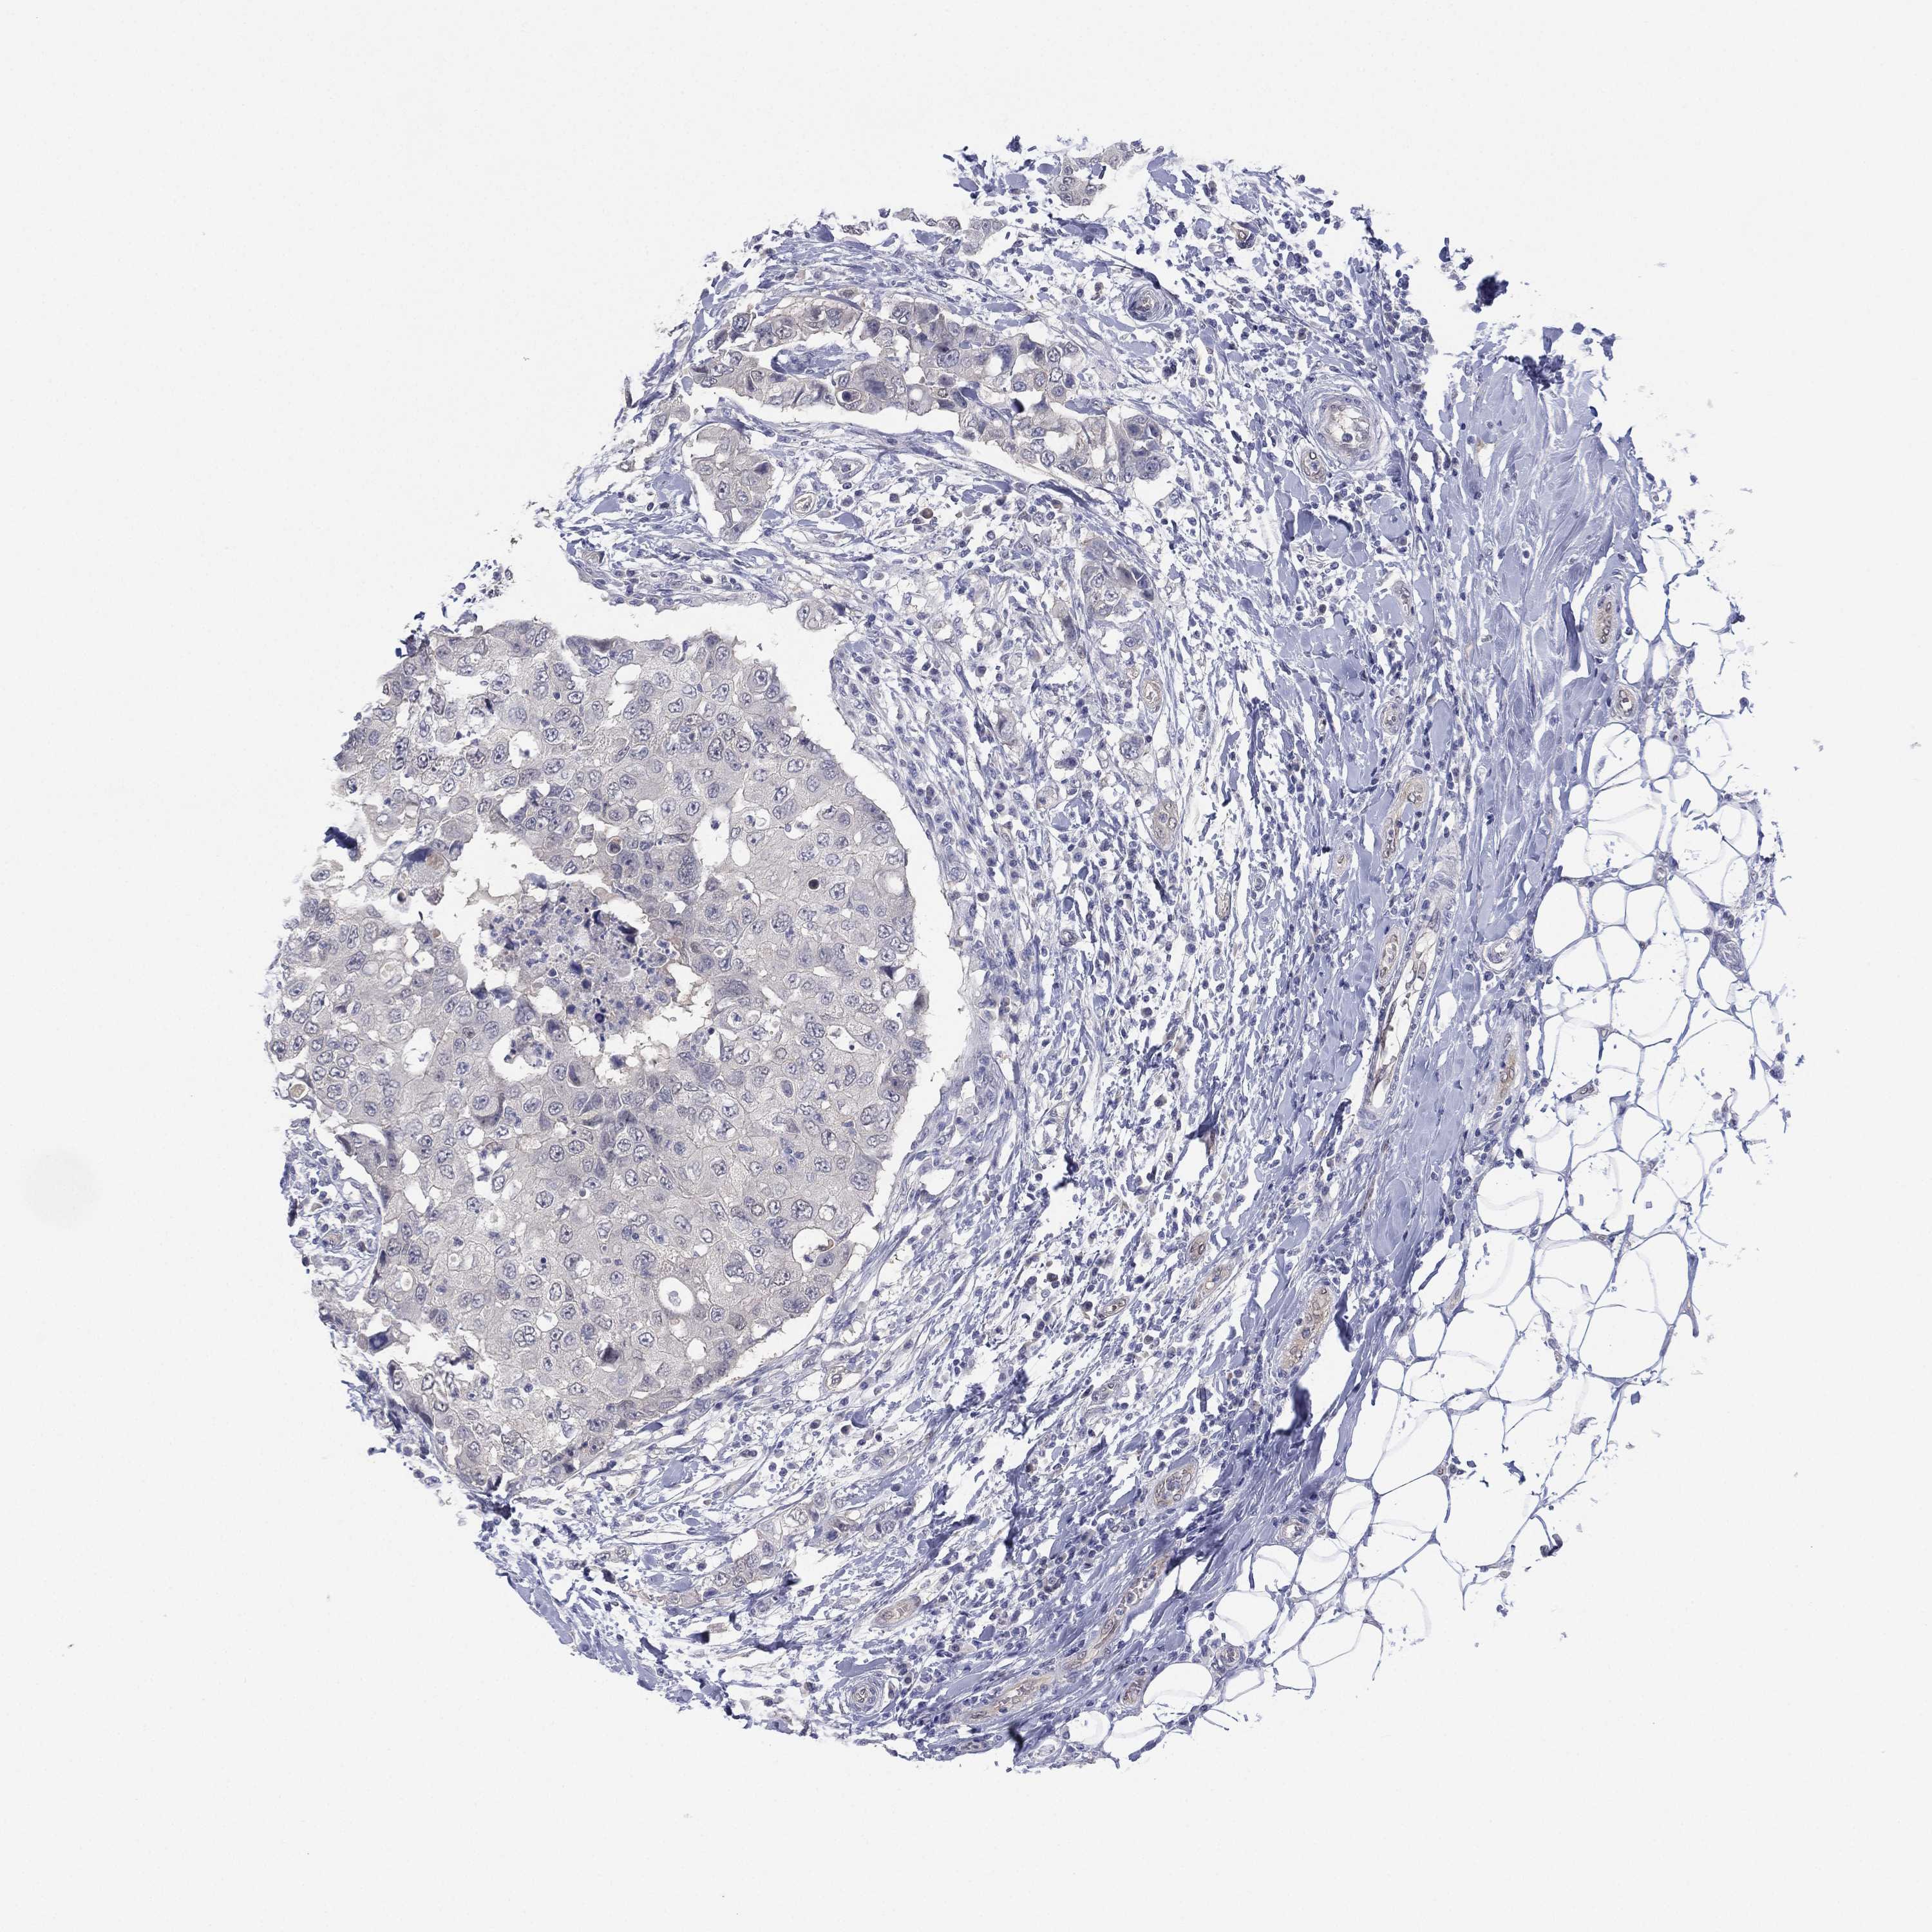

CANCER BREAST CANCER Show tissue menu

BRCA TCGA BRCA VALIDATION PROTEIN EXPRESSION

ANTIBODIES

AND

VALIDATION